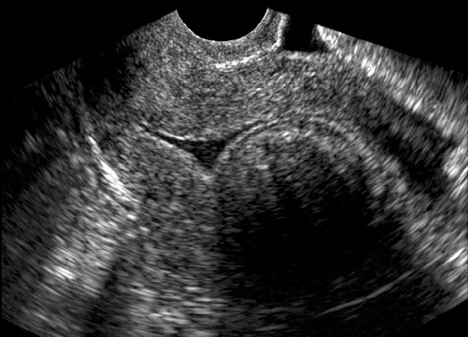

Útero septado pode ser causa de infertilidade. Certo ou errado?

Certo.